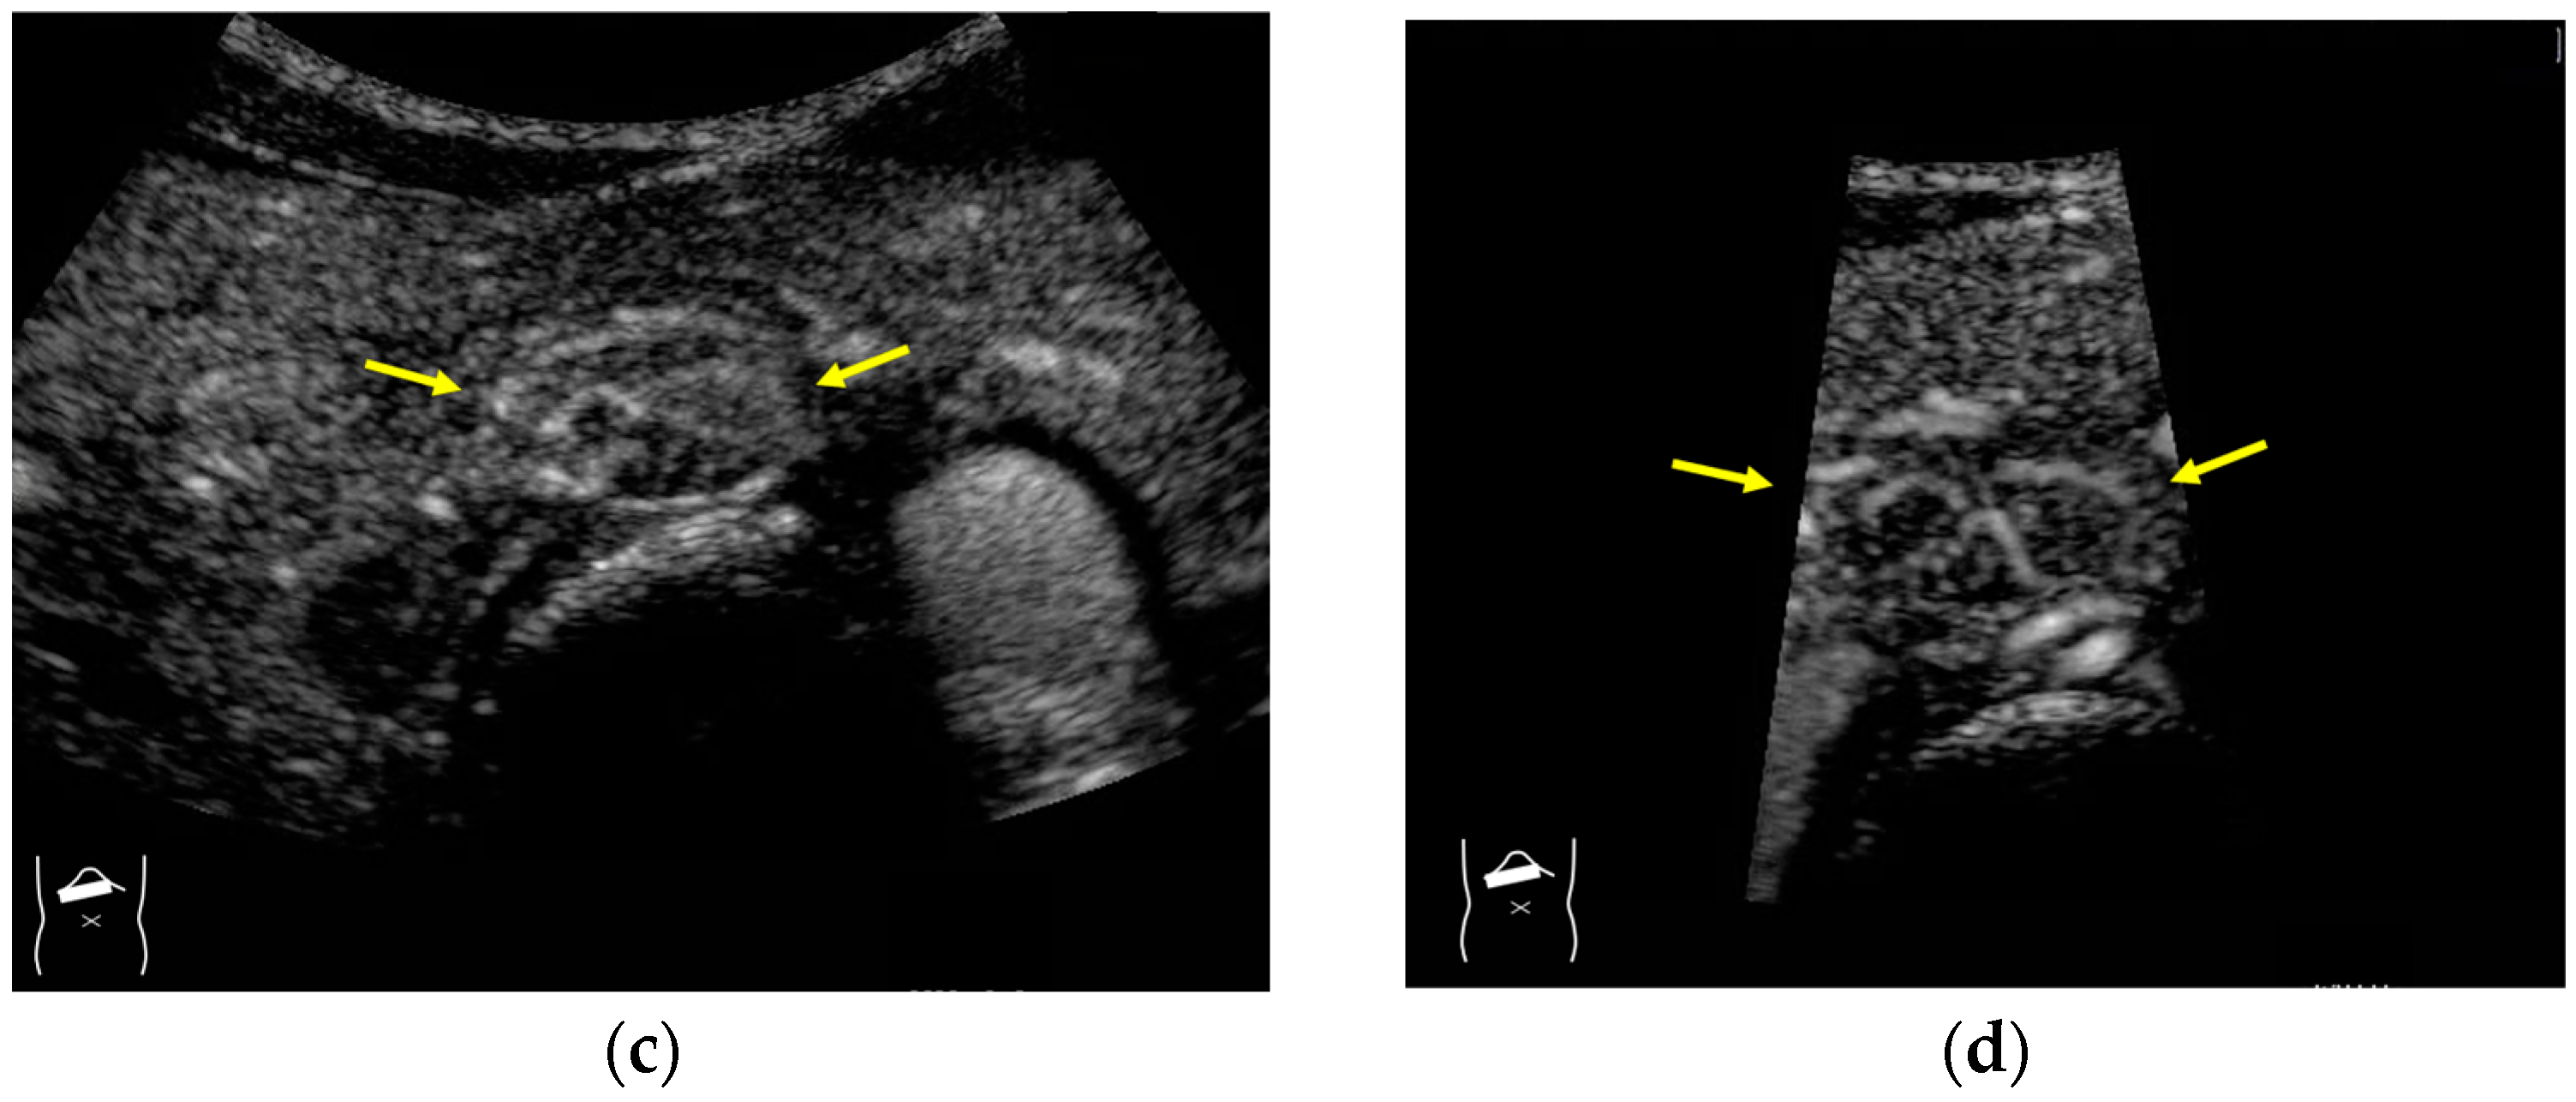

3.1.3. Range-Ambiguity Artifacts (RAAs)

- Naganuma, H.; Ishida, H.; Funaoka, M.; Fujimori, S.; Okuyama, A.; Odashima, M.; Takeuchi, S.; Hanaoka, A. Mobile echoes in liver cysts: A form of range-ambiguity artifact. J. Clin. Ultrasound 2010, 38, 475–479. [Google Scholar] [CrossRef]

- Naganuma, H.; Ishida, H.; Nagai, H.; Ogawa, M.; Ohyama, Y. Range-ambiguity artifact in abdominal ultrasound. J. Med. Ultrason. 2019, 46, 317–324. [Google Scholar] [CrossRef] [PubMed]